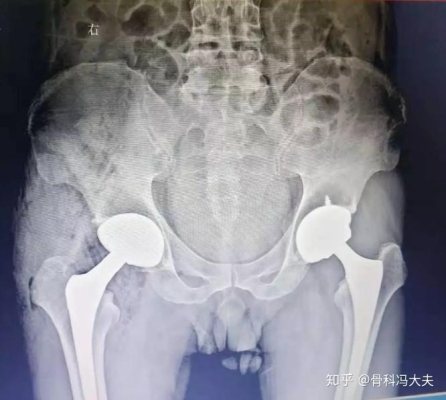

圖片來源于網(wǎng)絡(luò),侵刪